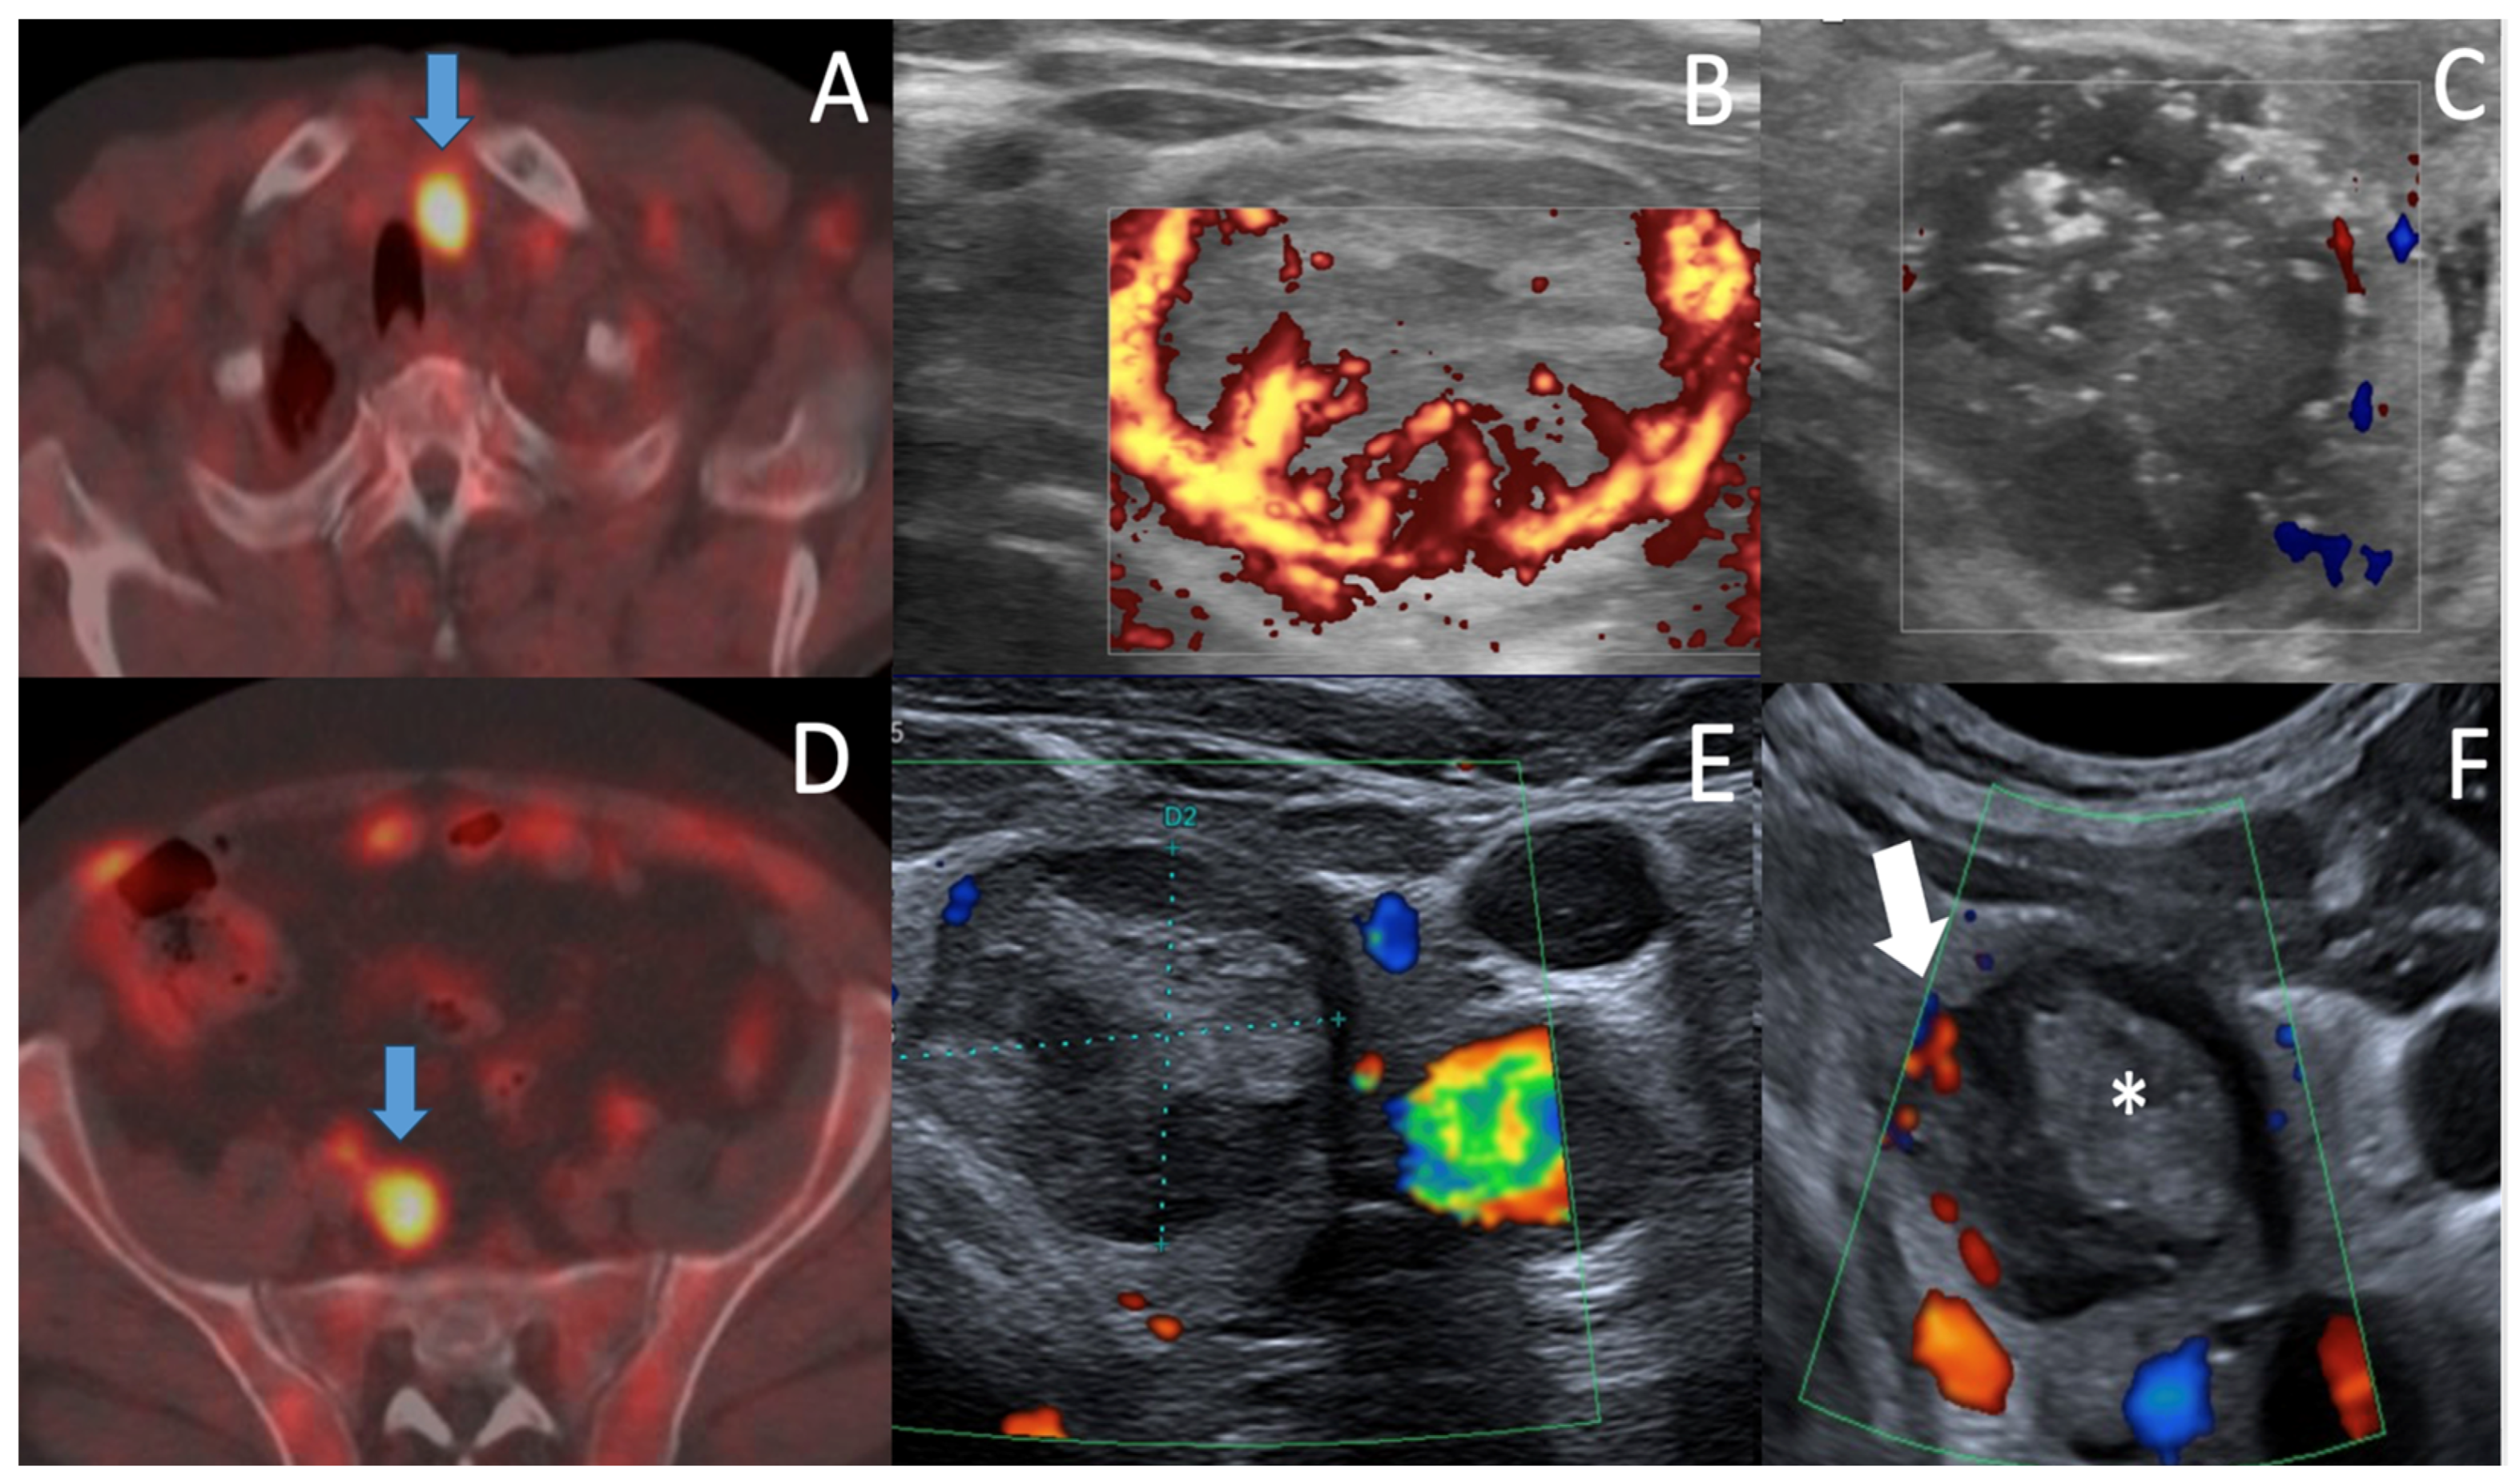

| Color Doppler/MVI/CEUS | Color Doppler/MVI | ||